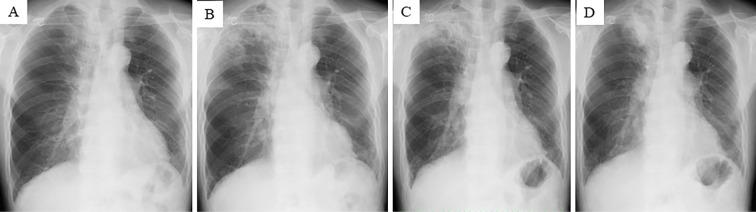

A 69-year-old man with systemic sclerosis and interstitial pneumonia presented with an abnormal shadow in the right upper lung lobe. A thoracoscopic needle biopsy was performed on the right upper lobe lesion, and Mycobacterium malmoense was identified by 16S rRNA and rpoB gene sequencing. Surgical treatment was performed to obtain a radical cure, and lung squamous cell carcinoma and M. malmoense infection were detected in the resected specimen. We herein report the first case of the successful treatment of a patient with pulmonary M. malmoense infection and concomitant lung squamous cell carcinoma.

一名患有系统性硬化症和间质性肺炎的69岁男性,右上肺叶出现异常阴影。对右上叶病变进行了胸腔镜针吸活检,通过16S rRNA和rpoB基因测序鉴定出马尔默分枝杆菌。为实现根治进行了手术治疗,在切除标本中检测到肺鳞状细胞癌和马尔默分枝杆菌感染。我们在此报告首例成功治疗肺部马尔默分枝杆菌感染合并肺鳞状细胞癌患者的病例。